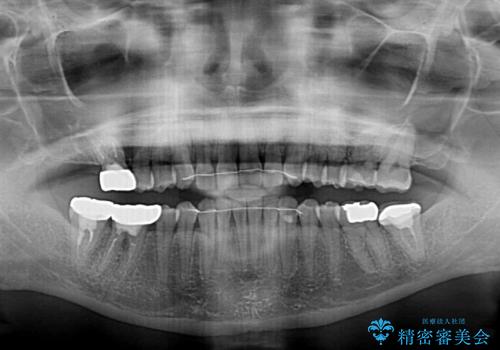

インビザラインにより下顎前歯の隙間を閉じるとともに、奥歯の咬み合わせを改善させることとしました。

矯正治療後には、銀歯のクラウンをセラミッククラウンへ替える補綴治療を行うこととしました。

左右奥歯の咬み合わせを変更させる必要があったため、治療期間は長くなることが予想されました。

1日22時間以上の装着時間をしっかりと守ってくださったので、順調に治療を進めることができました。